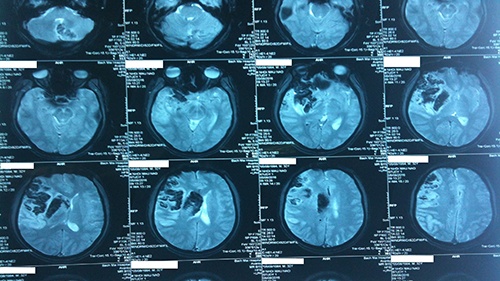

Chụp cộng hưởng từ (MRI) não là một kỹ thuật chẩn đoán hình ảnh dùng để đánh giá và phát hiện các tổn thương ở não. Đây cũng là phương pháp tối ưu vì không xâm lấn và ít gây ảnh hưởng đến sức khỏe của người bệnh cũng như cơ quan chụp.

Kết quả thu được thông qua chụp cộng hưởng từ não có thể hỗ trợ bác sĩ chẩn đoán một cách nhanh chóng, chính xác các bất thường tại não bộ, đặc biệt là trong các trường hợp như u não, viêm nhiễm, dị dạng mạch máu não... Bài viết sau đây sẽ mang đến những thông tin hữu ích về chụp cộng hưởng từ não và những lưu ý đối với kỹ thuật chẩn đoán hình ảnh này.

Chụp cộng hưởng từ não là một kỹ thuật chẩn đoán hình ảnh không gây đau, không xâm lấn và cung cấp hình ảnh 3D về các cấu trúc bên trong phần đầu, trong đó bao gồm não bộ.

So với các kỹ thuật chẩn đoán hình ảnh khác như chụp CT Scan hay chụp X-quang thì chụp cộng hưởng từ cung cấp hình ảnh khá chi tiết và sắc nét hơn. Đặc biệt, kỹ thuật MRI có độ nhạy khá tốt và có thể giúp phân biệt giữa mô bệnh và mô bình thường, có ý nghĩa đối với việc cung cấp hình ảnh về thành phần các nhu mô não trong chẩn đoán điều trị. Hiện tại, MRI là xét nghiệm hình ảnh nhạy cảm nhất trong đánh giá xác định những bất thường ở phần đầu (đặc biệt là não) so với các kỹ thuật hình ảnh khác.